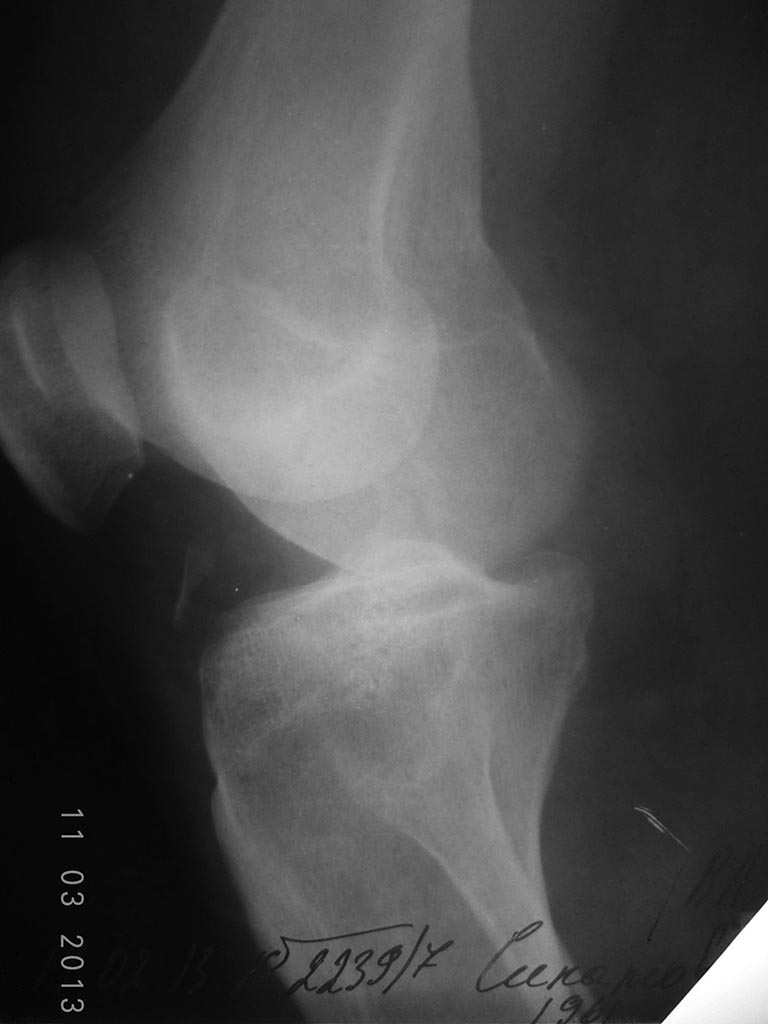

Боковая проекция Вашему вниманию.

В боковой проекции есть отрывной костный фрагмент от б/берцовой кости- посмотрите на предмет повреждения крестообразных связок. Также, учитывая высококинетический,по-видимому, характер повреждения - стоит обратить внимание на возможность повреждения всего задне-латерального связочного комплекса. Если есть возможность - МРТ.